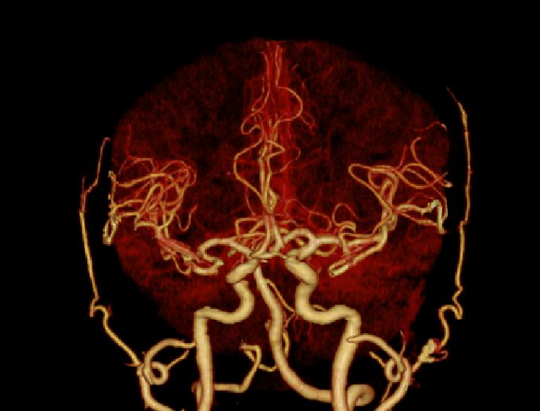

门控轴扫与螺旋扫描快速切换,一次造影注射即可实现高质量肺动脉、冠脉和主动脉成像,实现胸痛三联征的快速评估

随扫描曝光同步进行实时三维图像重建,在断层图像的基础上同时提供VR、MPR多维度的图像信息,辅助医生快速判断急性病症